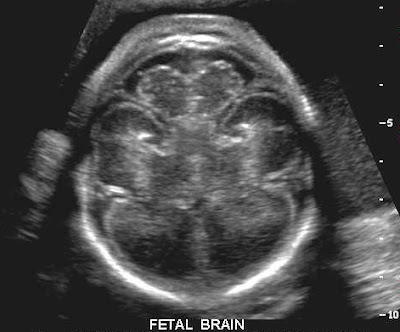

Ένα νέο τεστ διάγνωσης, μέσω υπερήχων, παρέχει τη δυνατότητα έγκαιρου εντοπισμού των ανθρώπων εκείνων που έχουν υψηλό κίνδυνο εγκεφαλικού.

Το νέο τεστ, σύμφωνα με το πρακτορείο Ρόιτερ, παρουσιάστηκε στο περιοδικό νευρολογίας “Neurology” από ερευνητές διαφόρων χωρών. Tο τεστ, που αφορά κυρίως όσους έχουν φραγμένη αρτηρία της καρωτίδας στο λαιμό και αντιμετωπίζουν μεγαλύτερο κίνδυνο εγκεφαλικού, ξεχωρίζει όσους έχουν ανάγκη από χειρουργική επέμβαση στην καρωτίδα λόγω του πολύ υψηλού κινδύνου που προκαλεί η στένωσή της, εξαιτίας συνήθως της δημιουργίας πλάκας από την υψηλή χοληστερίνη.

Οι ερευνητές πάντως διευκρίνισαν ότι η αξιοπιστία του τεστ (που συνδυάζει δύο υπέρηχους, ένα στην αρτηρία της καρωτίδας και ένα στις αρτηρίες του ίδιου του εγκεφάλου) πρέπει να επιβεβαιωθεί από άλλες έρευνες, ενώ επίσης δύσκολη θεωρείται η σωστή ερμηνεία των υπερήχων στον εγκέφαλο.